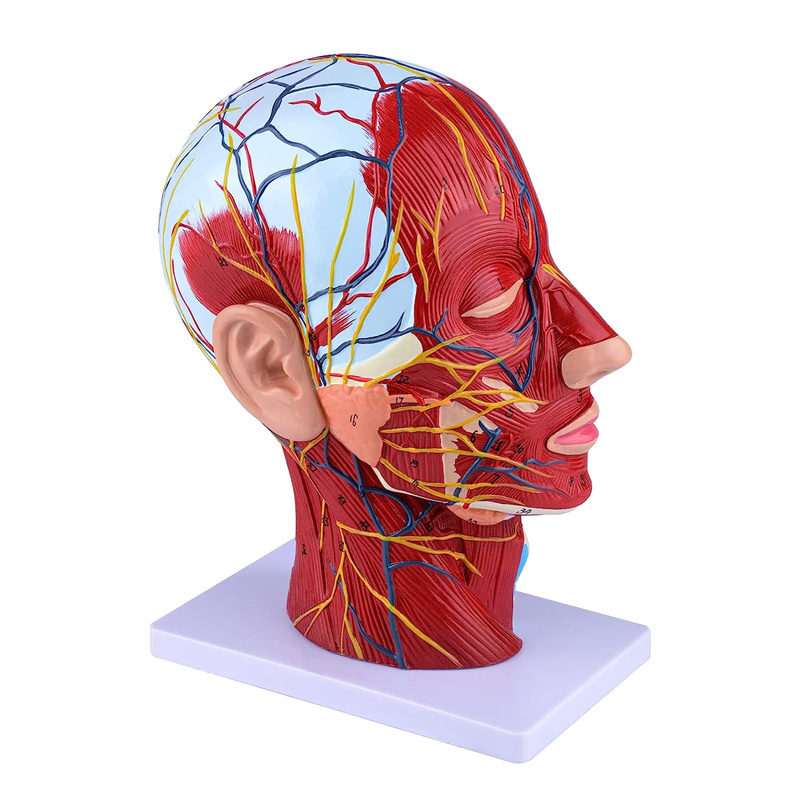

| Izici | Imodeli ikhombisa i-morphology yendawo yezinhlangothi zangaphakathi nezingaphandle zengxenye ye-Median Sagittal yekhanda nentamo, kanye nezinhlaka zemithambo yegazi nezinzwa, futhi kunezingxenye ezingama-84 ezibonisa izibonakaliso zizonke. |

【1: 1 I-Lifesise】 Ingxenye ye-Median ye-Median ye-1: 1 yemvelo enkulu yemvelo & imodeli yemisipha yemisipha ye-nearal ye-nearal ye-nearal (uhlangothi olungakwesokudla). Umsebenzi omuhle. Ukunikeza uhla oluphelele lwezici ze-anatomical.

【Imodeli ye-Neurovascular yemisipha ekhethekile enemininingwane eminingi, izinombolo ezimakwe kakhulu, izindlebe ezivinjelwe, zijulisa ukuqonda kwemisipha engaphezulu, imikhumbi, izinzwa kanye nezinhlaka zangaphakathi zekhanda nentamo. I-Red-artery, i-Blue-Vein, i-Yellow-Nerve.

Le modeli ikhombisa imininingwane yekhanda leNhloko yeNhloko yeNhloko ne-Mid sagittal yomuntu. kufaka phakathi okuphezulu

izicubu zobuso obudaluliwe; Imithambo yegazi engekho emthethweni nezinzwa zobuso nesikhumba; Izakhiwo ezingaphakathi

ye-parotid gland nepheshana lokuphefumula elingaphezulu; isakhiwo sesigaba se-sagittal somgogodla wesibeletho.

Le modeli ikhombise i-morphology yendawo yezingxenye zekhanda nentamo yekhanda nentamo kanye nezinhlaka zayo ze-vascular nezinzwa, ezinazo ingqikithi yezinkomba eziyi-100.

Le modeli iyinhloko enkulu yemvelo nemodeli ye-neurovascular yemisipha eyindilinga, isakhi esingu-1, ekhombisa imininingwane yekhanda lelungelo lomuntu kanye nentamo kanye nengxenye ye-Median Sagittal, okubandakanya imisipha engemihle yobuso, imithambo ephakeme yobuso obukhulu bobuso kanye nesikhumba, izinzwa nokwakheka kwempilo kwe-parotid gland kanye nepheshana lokuphefumula elingaphezulu, kanye nesakhiwo seSigaba se-sagittal somgogodla wesibeletho